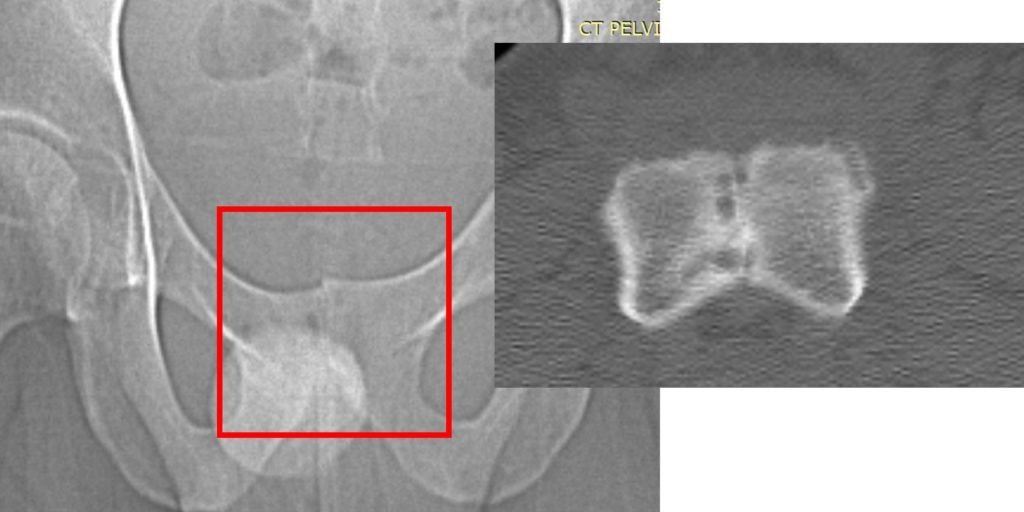

- X-rays: May reveal changes in bone structure, such as irregularities or reactive bone formation near the pubic symphysis.

When the patient resumed running just two months after the fusion surgery, the stress that the SI joint would typically absorb was instead redirected to the symphysis pubis. This excessive strain led to the rapid onset of severe osteitis pubis. Imaging studies (X-ray and CT scan) revealed significant damage: the normal space within the symphysis pubis, which houses the fibrous disc, had disappeared entirely, and the surrounding bone exhibited marked erosion.

The images below, taken several months after the orthobiologic procedure, demonstrate significant improvement in the condition of the symphysis pubis joint.

The follow-up images indicate a restored joint space in the symphysis pubis, with improvements in the surrounding bone structure. The patient reported noticeable improvement, noting that 80–90% of his symptoms had diminished and that he experiences minimal daily discomfort. This outcome illustrates the potential role of orthobiologic procedures in supporting joint health and function.